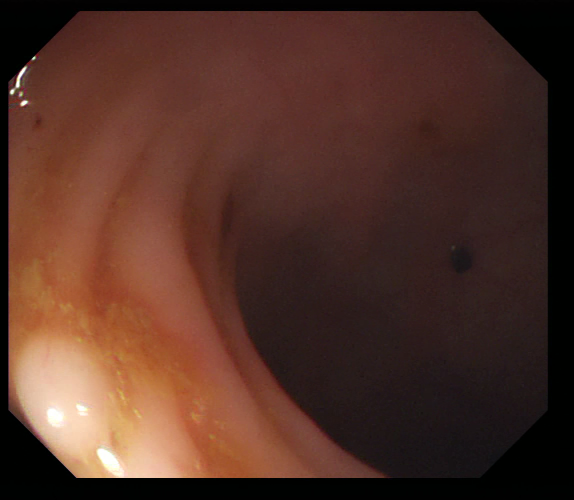

Figure 1: Polyp visual aspects have a wide variety in terms of shape and color. Four different polyps sampled from the different databases considered in this work: (a) Kvasir-Seg [19], (b) CVC-ClinicDB [5], (c) CVC-ColonDB [4], (d) ETIS [29].

The large bowel within the human gastrointestinal tract can be affected by different diseases, among which, Colorectal Cancer (CRC) is particularly concerning. CRC represents the second most common cancer type in women and third most common for men [15]. Gastro-intestinal polyps are known precursors of this type of cancer [34], being present in almost half of the patients over 50 undergoing screening colonoscopies [31]. This kind of lesions show a wide range of shapes and visual appearances, as shown in Fig. 1, turning its identification and segmentation into a challenging problem.